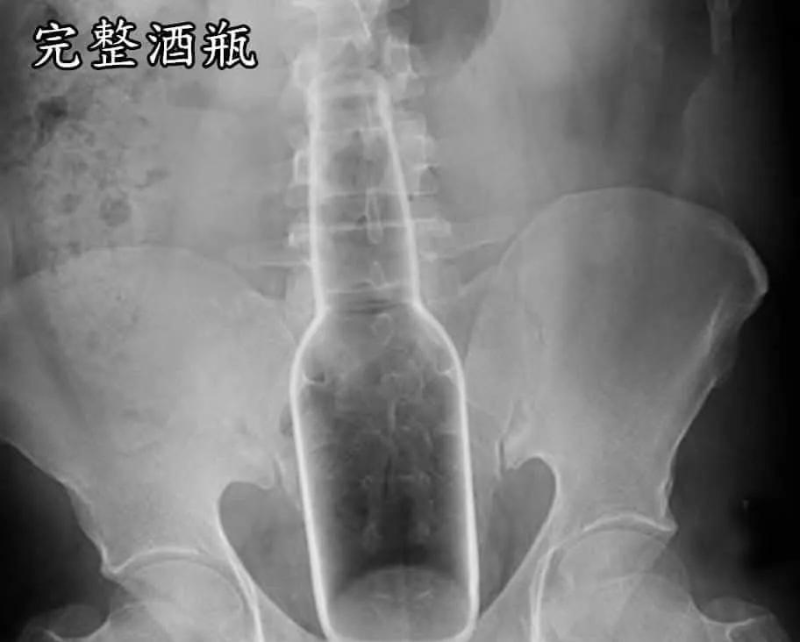

醫生公開「年度直腸內最怪案例」

醫師“衛教宣導”:拜託大家,屁眼是“消化器官”不是“性器官”,請不要為了“性樂趣

”,亂塞異物進入肛門!謝謝!!

https://i.imgur.com/dQNcVCA.jpeg 酒瓶

![[圖]](https://imgur.disp.cc/4d/dQNcVCA.jpeg)